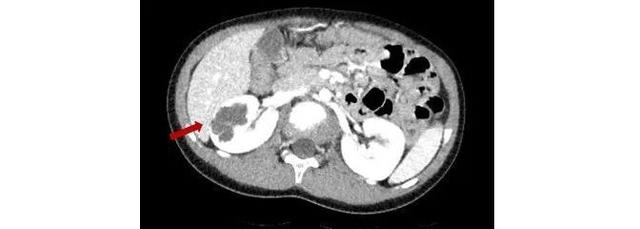

数月前一名5岁的小树也因发现右肾多房囊性肾肿瘤慕名找到新华医院崔心刚教授团队进行保肾手术。崔教授在仔细阅片后,发现该囊性肿瘤同样也是完全内生型,肿瘤大小接近4cm,且肿瘤的形态不规则,在保肾手术过程中发生肿瘤囊壁破裂的风险极大。崔教授在利用术中超声精确定位肿瘤边界后,顺利完整地切除了该肿瘤,很好地保留了残余肾功能。